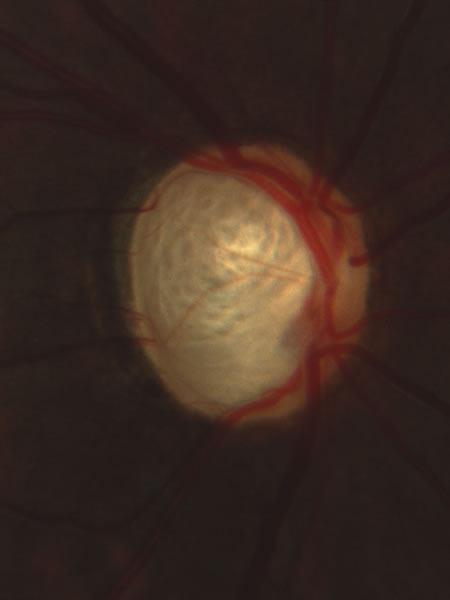

Fig. 30. Total cupping of the disc caused by use of topical corticosteroid. Severe cupping can occur without accompanying atrophy of peripapillary tissue, although in some cases, progressive cupping is accompanied by progressive atrophy of adjacent retinal pigment epithelium and choroid.

Fig. 31. Advanced glaucomatous cup with complete loss of tissue at the upper and lower poles of the disc, a splinter hemorrhage nasally, and a glaucomatous halo of atrophic choroid and retinal pigment epithelium. The disc itself is separated from the peripapillary β zone by a conspicuous white stripe of the scleral lip.